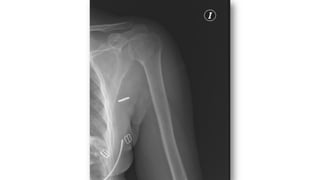

FRACTURA HUMERO

• 5% de las fracturas del adulto, 75% en 1/3 superior

• Más frecuentes en ancianos (osteoporosis)

• Tratamiento:

• Conservador: cuello quirúrgico con impactación (ancianos)

• Quirúrgico: el resto

• Complicaciones

• Seudoartrosis

• Consolidación defectuosa

• Necrosis avascular

• Lesión nerviosa ó vascular

• Rigidez-capsulitis.

• Fx diáfisis: más frecuente en jóvenes o ancianos con fx patológica

• Clasificación de Neer: relación entre troquín, troquíter,

segmento articular y diáfisis

• Divide las fracturas en función de los desplazamientos de

estos segmentos

• FX desplazada: tiene 2, 3 o 4 segmentos, fractura-luxación,

fractura articular

• Separación >1cm o ángulo >45º